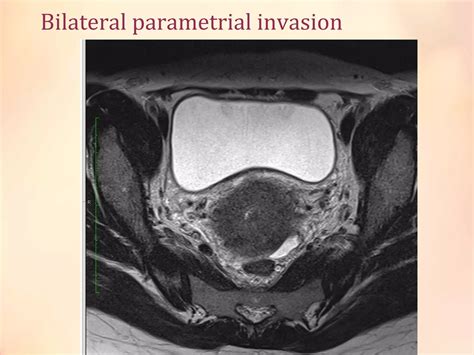

• MRI (Magnetic Resonance Imaging): Highly effective for looking at soft tissues and determining the tumor size and local spread.